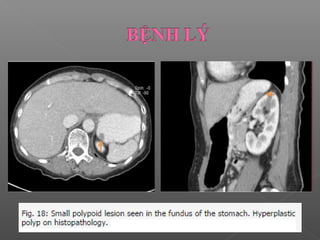

 Polyp dạ dày (Polypoidal presentations)

 Một polyp nhỏ dễ bị bỏ qua do không tìm kiếm hoặc do nghĩ

là nếp niêm mạc-> mặt phẳng tái tạo, nội soi ảo.

 Trong các Polyp thì Polyp tăng sản hay gặp nhất.

 Trên CT: polyp tăng sản thường là tổn thương không có

cuống đường kính 5- 10 mm nằm ở phía sau đáy vị hoặc

phình vị

 Một polypnhỏ dễ bị bỏ qua do không tìm kiếm hoặc do nghĩ là nếp niêm mạc-> mặt phẳng tái tạo, nội soi ảo.  Trong các Polyp thì Polyp tăng sản hay gặp nhất.  Trên CT: polyp tăng sản thường là tổn thương không có cuống đường kính 5- 10 mm nằm ở phía sau đáy vị hoặc phình vị